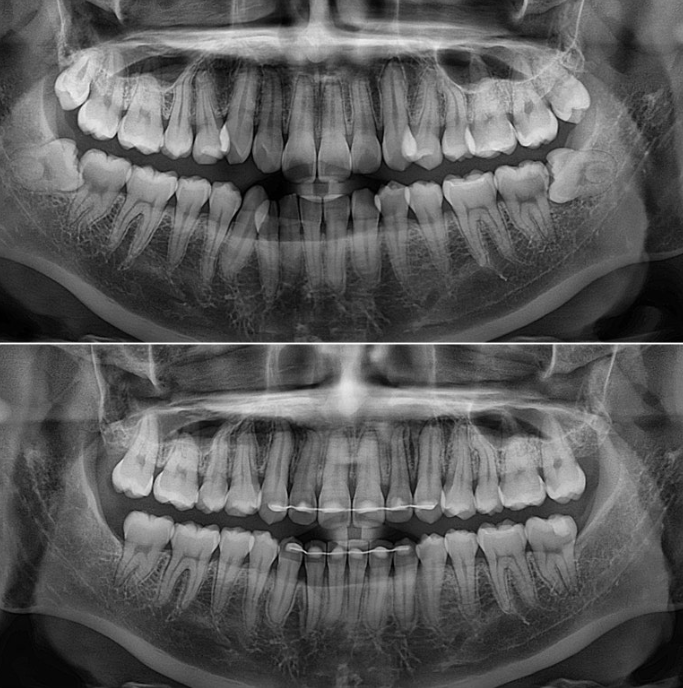

발치가 필요할 정도의 덧니나 돌출입은 아니여서 비발치로 매복된 사랑니를 빼고 사랑니 공간을 이용하여 어금니를 뒤로 이동 시키는 치료를 권유드렸습니다.

사랑니 공간을 이용하여 어금니를 뒤로 밀기 위한 교정용 나사를 입천장에 심고 진행했습니다.

총 치료기간은 1년 8개월 재제작은 1회 했습니다.

치근흡수도 없고 치근평행도도 좋습니다.